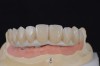

The final restorative solution can be either fixed or removable. Fixed solutions may include: computer-aided designed/computer-aided manufactured (CAD/CAM) fixed prostheses with a titanium (Figure 8 and Figure 9) or zirconia (Figure 10 and Figure 11) framework; fixed prostheses with a CAD/CAM-designed titanium or zirconia framework with acrylic veneering (Figure 12); or fixed prostheses with cast metal and veneering porcelain. Removable solutions may include a milled bar overdenture with attachments, such as locators or an MK1 Attachment (MK1 Dental Attachment GMBH, www.MK1.de) (Figure 13). Removable solutions that allow for simpler hygiene-related practices may be beneficial for elderly patients. In addition, removable solutions may be necessary for patients who require sufficient lip support, as the flange on a removable solution can assist in supporting the contours of the face. It is important to discuss the relative advantages and disadvantages of fixed and removable solutions during the informed consent process.

Fig 9. Intraoral view of the titanium bridge framework with individual lithium-disilicate crowns.

Figure 9

Fig 10. The full-arch zirconia framework with individual lithium-disilicate crowns, which were individually luted in the laboratory.

Figure 10